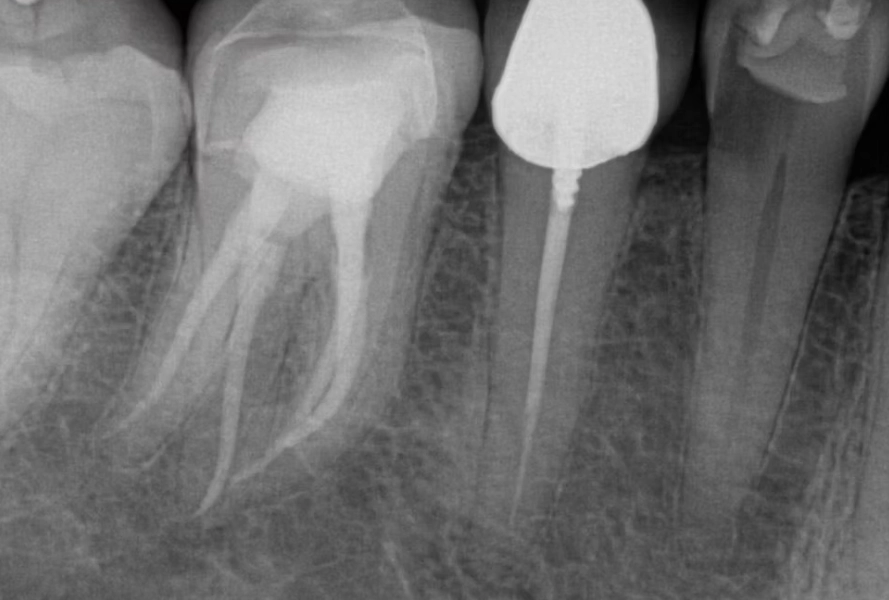

The biggest headache with premolar root canals is their root structure. While a front tooth typically has one simple root canal, a premolar can be a surprise package.

| Upper First Premolar | 2 roots, 2 canals (very common) | Often has two separate roots. Missing one canal is a leading cause of failed treatment. |

| Upper Second Premolar | 1 root, but often 2 canals inside it | The single root frequently splits into two canals (a "web" shape), easy to miss. |

| Lower Premolars | 1 root, 1 canal (usually) | Generally simpler, but the canal can be curved or narrow, requiring fine instruments. |

This variability is why some premolar root canals feel straightforward, while others require the precision of a specialist (an endodontist). I once had a patient whose upper first premolar had three separate canals—a configuration you won't find in any textbook but happens more than people think. If a dentist isn't using a dental microscope and only takes one standard X-ray, they might completely miss an extra canal, leaving infected tissue behind. That tooth will hurt again in six months, guaranteed.

First, good imaging is non-negotiable. A periapical X-ray shows the length of the roots. For complex cases, a 3D cone beam CT scan might be used. This gives a detailed map, crucial for navigating those tricky, multi-canal premolars. Your dentist will also administer local anesthesia. The idea that root canals are painfully done is a complete myth—if you feel sharp pain, speak up. More anesthetic can be given. You should only feel pressure.